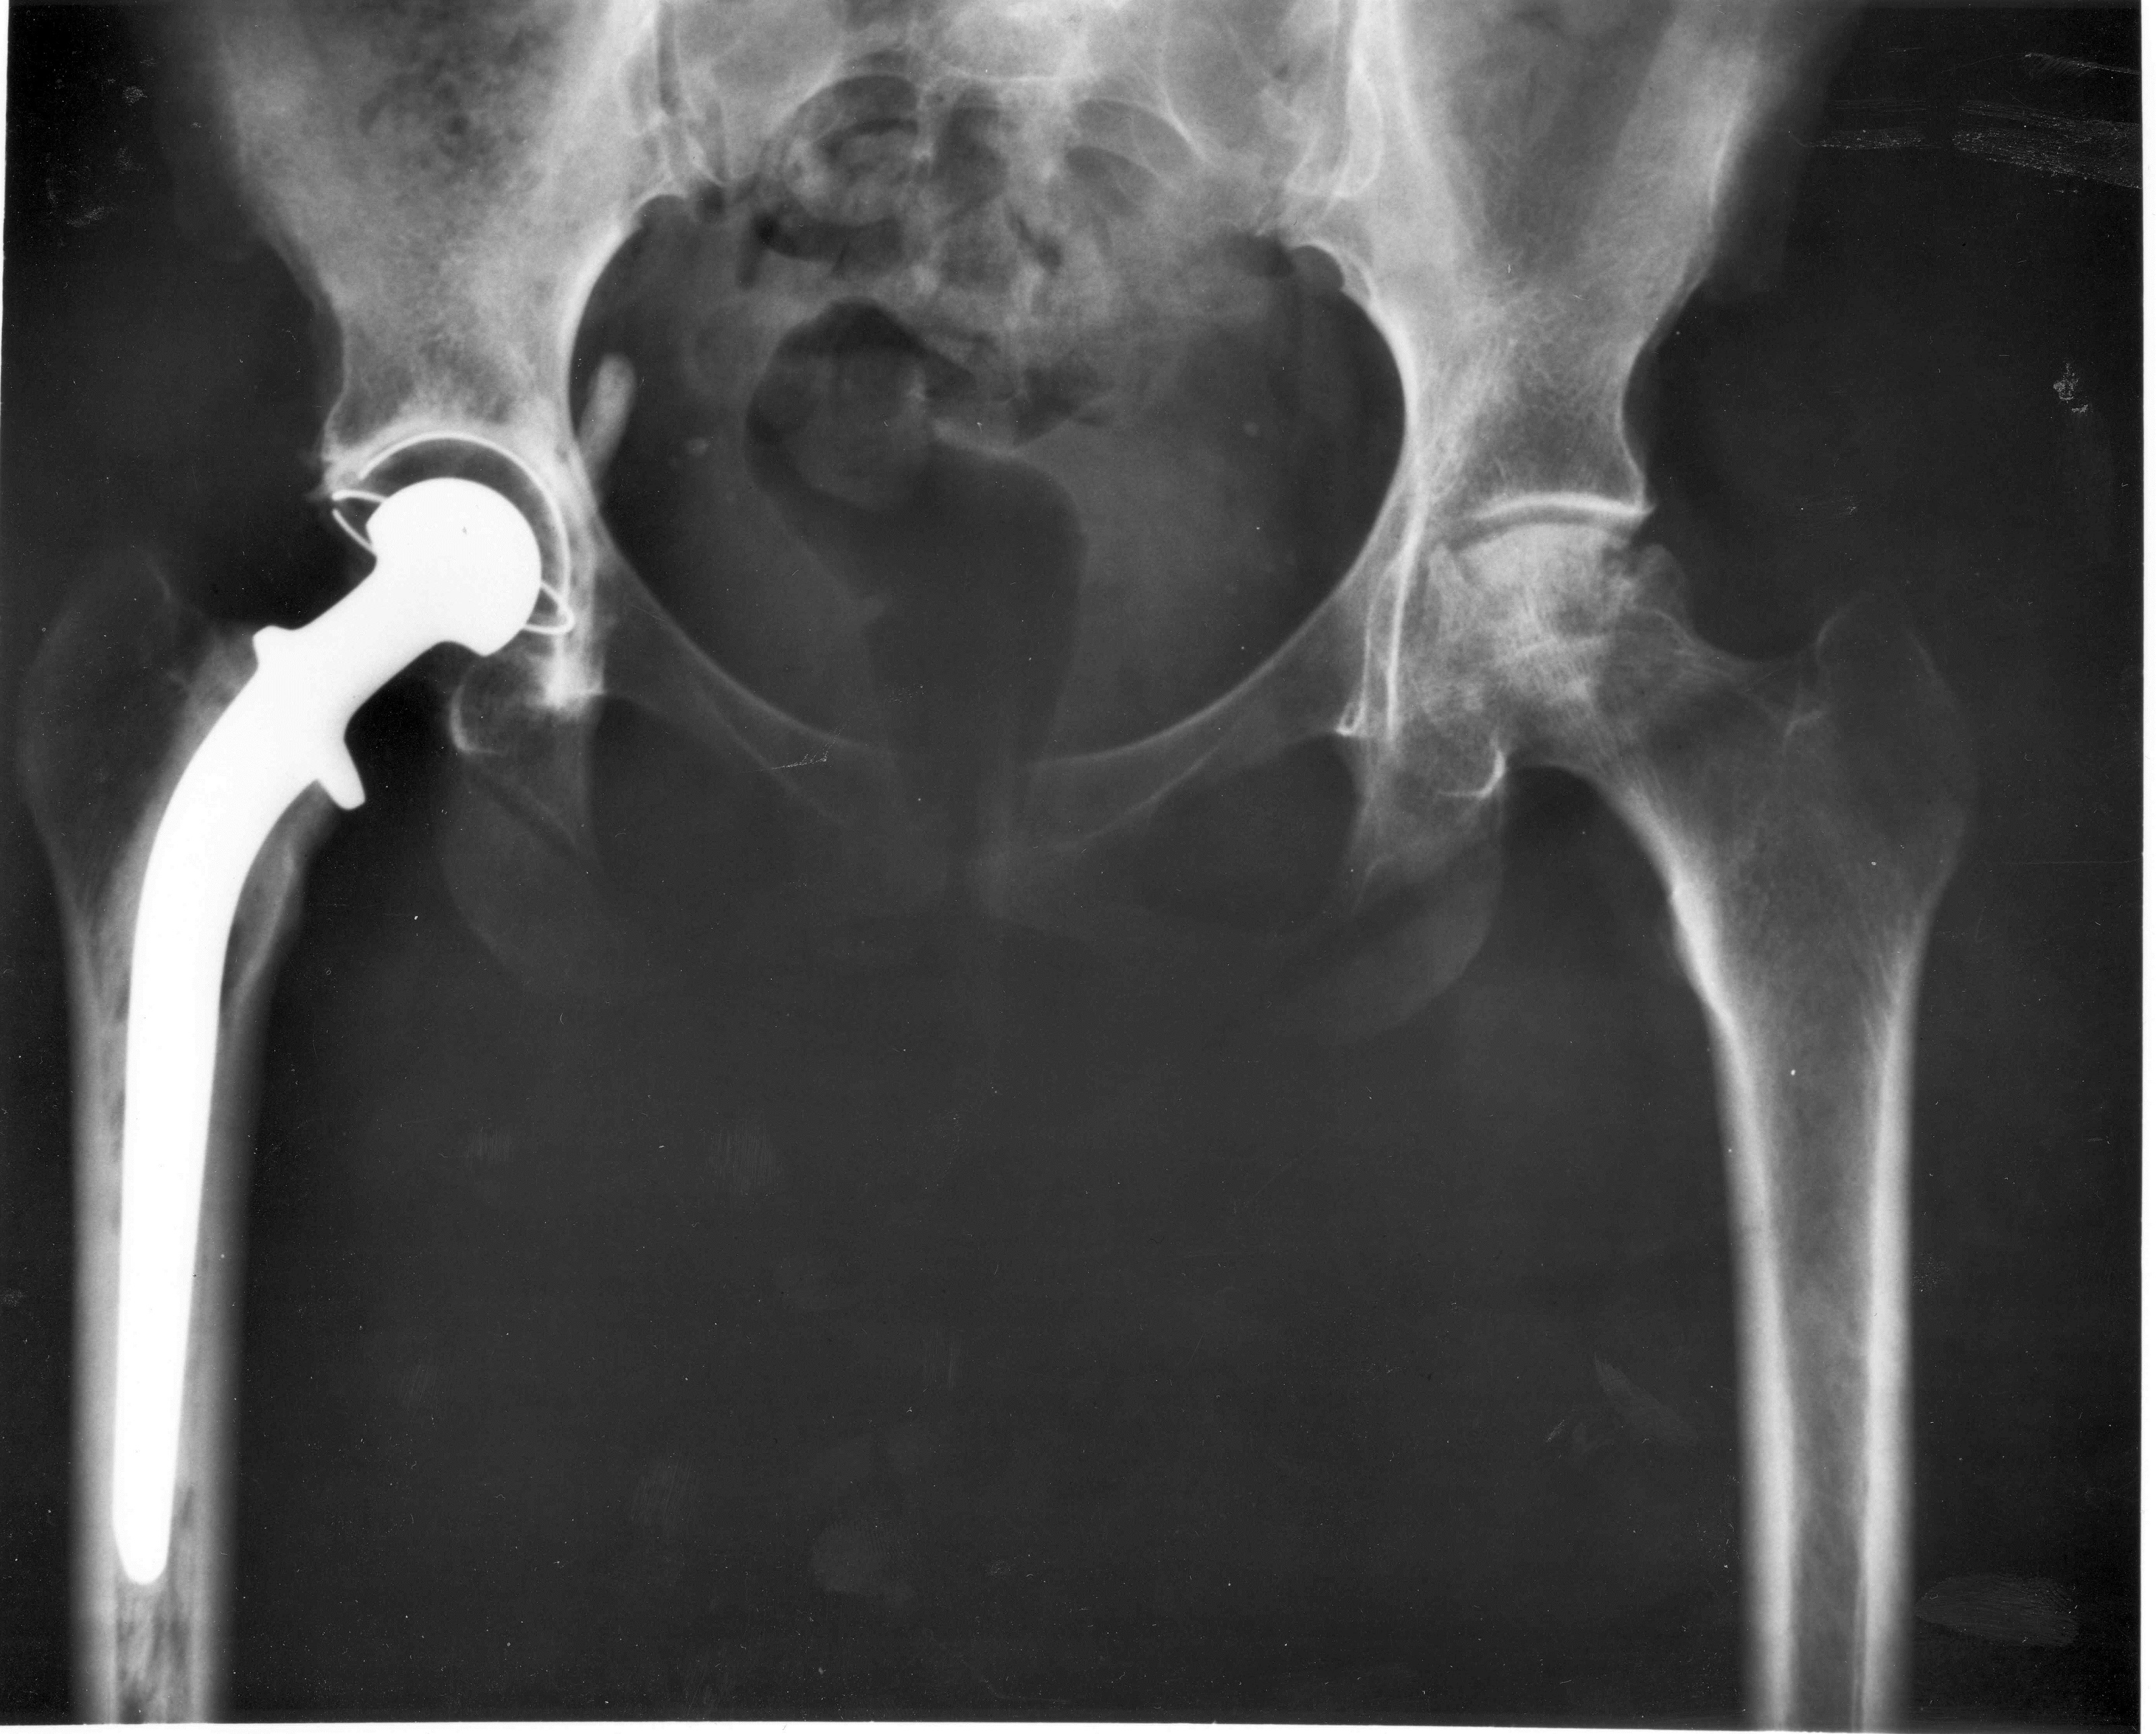

Tento kov ocení zejména armáda. Je potřebný při výrobě nadzvukových stíhaček, raket, řízených a dělostřeleckých střel, tanků a další vojenské techniky. Ocení ho také chirurg v podobě kvalotního nástroje i člověk potřebující kloubní implantát. Je to: